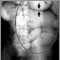

Intestinal obstruction is a partial or complete blockage of the bowel that results in the failure of the intestinal contents to pass through.

Tests that show obstruction include: